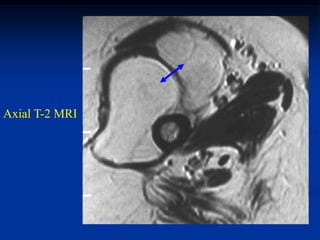

Case #1213

46 year male with

lymphangioma arm

Another T-2 MRI

showing 2 lesions

Coronal T-2 MRI

vein

showing lymphangioma

next to cephalic vein

Case #1213 46 yearmale with lymphangioma arm Axial PD MRI

Coronal T-2 MRI vein showing lymphangioma next to cephalic vein